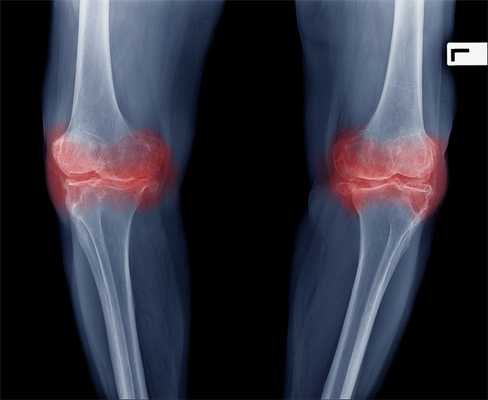

Рентгенологическое исследование помогает поставить диагноз, но не дает прогнозов по дальнейшему развитию симптомов заболевания. Рентгенограммы могут показать обширные изменения, но это не всегда означает в клинике сильную боль или нетрудоспособность пациента.

По данным исследователей, у 76% пожилых людей, предъявляющих жалобы на боль в коленях, на рентгенограммах обнаруживается гонартроз. [2] [7] [17] По статистике, чаще заболеванием страдают женщины, что связано с гормональной перестройкой после 45 лет. [12] [19]